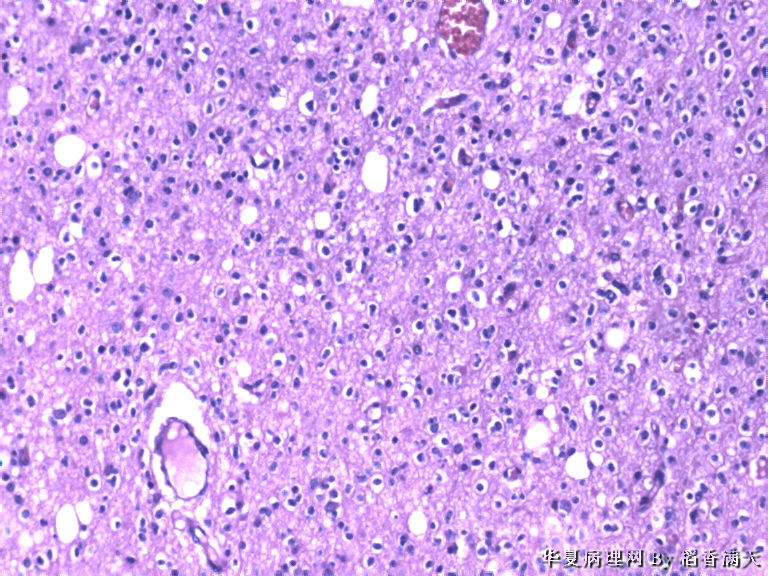

患者,女,39岁,发现左额叶占位1天入院,MRI示左额叶占位,术中见肿块约2*2cm,乳白色,包块质韧。

少突胶质细胞瘤

favor oligo.